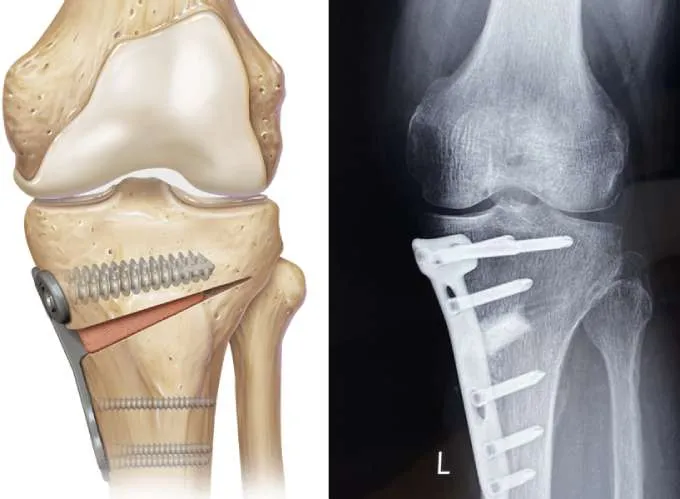

Is high tibial osteotomy major surgery?

Yes, high tibial osteotomy (HTO) is considered a major orthopedic surgery because it involves cutting and realigning the tibia. However, it is less invasive than total knee replacement and aims to preserve your natural joint. With modern techniques and experienced surgeons like Dr. Divya Ahuja, the risks are minimized, and recovery outcomes are excellent.

What is the purpose of HTO?

The main purpose is to realign the knee joint, shift body weight away from the arthritic side, relieve pain, and preserve the natural joint. It allows patients to stay active longer before considering knee replacement.